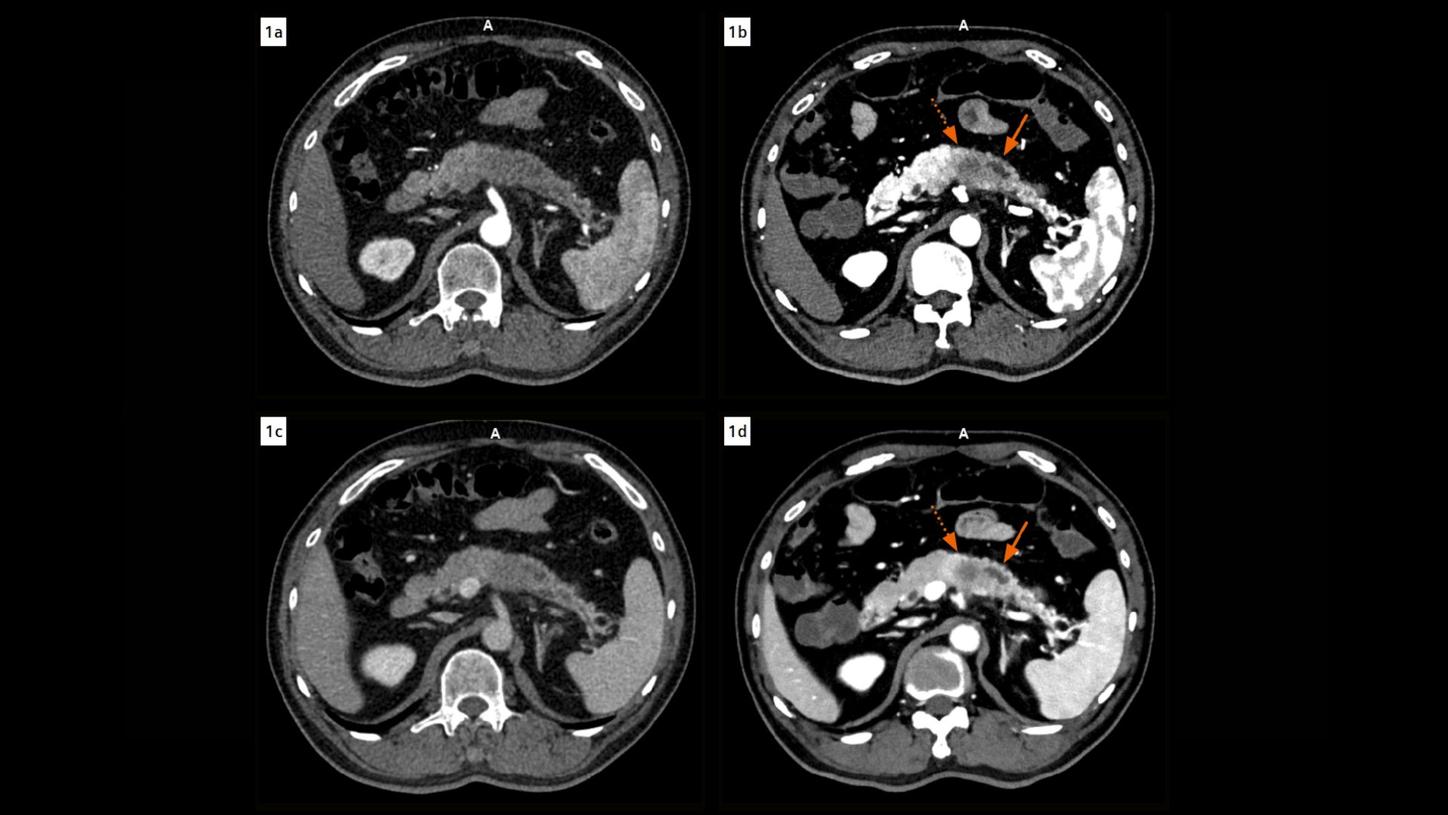

Fig. 1:Axial images acquired during the arterial (Figs. 1a & 1b, EID at 1 mm, PCD at 0.4 mm) and venous phases (Figs. 1c & 1d, 3 mm) show a comparison of CT findings in the pancreas in EID (Figs. 1a & 1c) and PCD CT images (Figs. 1b & 1d). The fluid attenuation within the main pancreatic duct (arrows) adjacent to the tumor appears heterogeneous in EID CT images, however, clearly homogeneous in PCD CT images, ruling out the suspicion of an intraductal tumor spread. The tumor is distinctly delineated with clear margins in the PCD CT images (dotted arrows). Note the improved contrast in PCD CT images using VMIs displayed at 50 keV.